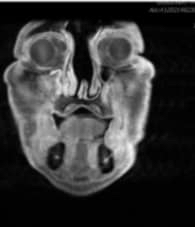

嗅神經母細胞癌的手術前與手術後對照。

二○二二年九月,一位男士被轉診到花蓮慈濟醫院耳鼻喉科看診,轉診前已經看過好幾個神經外科和眼科,主治醫師周昱甫回憶當時:「看到阿伯額頭凸凸,眼距開開,檢查後發現他的腫瘤從大腦額葉,到雙側眼眶到鼻腔上部,占據整個前顱底⋯⋯」,這位先生罹患的是「嗅神經母細胞癌」。

他擔心這位七十四歲的病人能不能承受這樣的大手術,於是以「內視鏡顱底手術」清除百分之九十五以上的腫瘤。病人術後沒有不適症狀,三天後就出院了,而且術後一個月回診,傷口恢復良好,斷層掃描也沒有發現腫瘤。